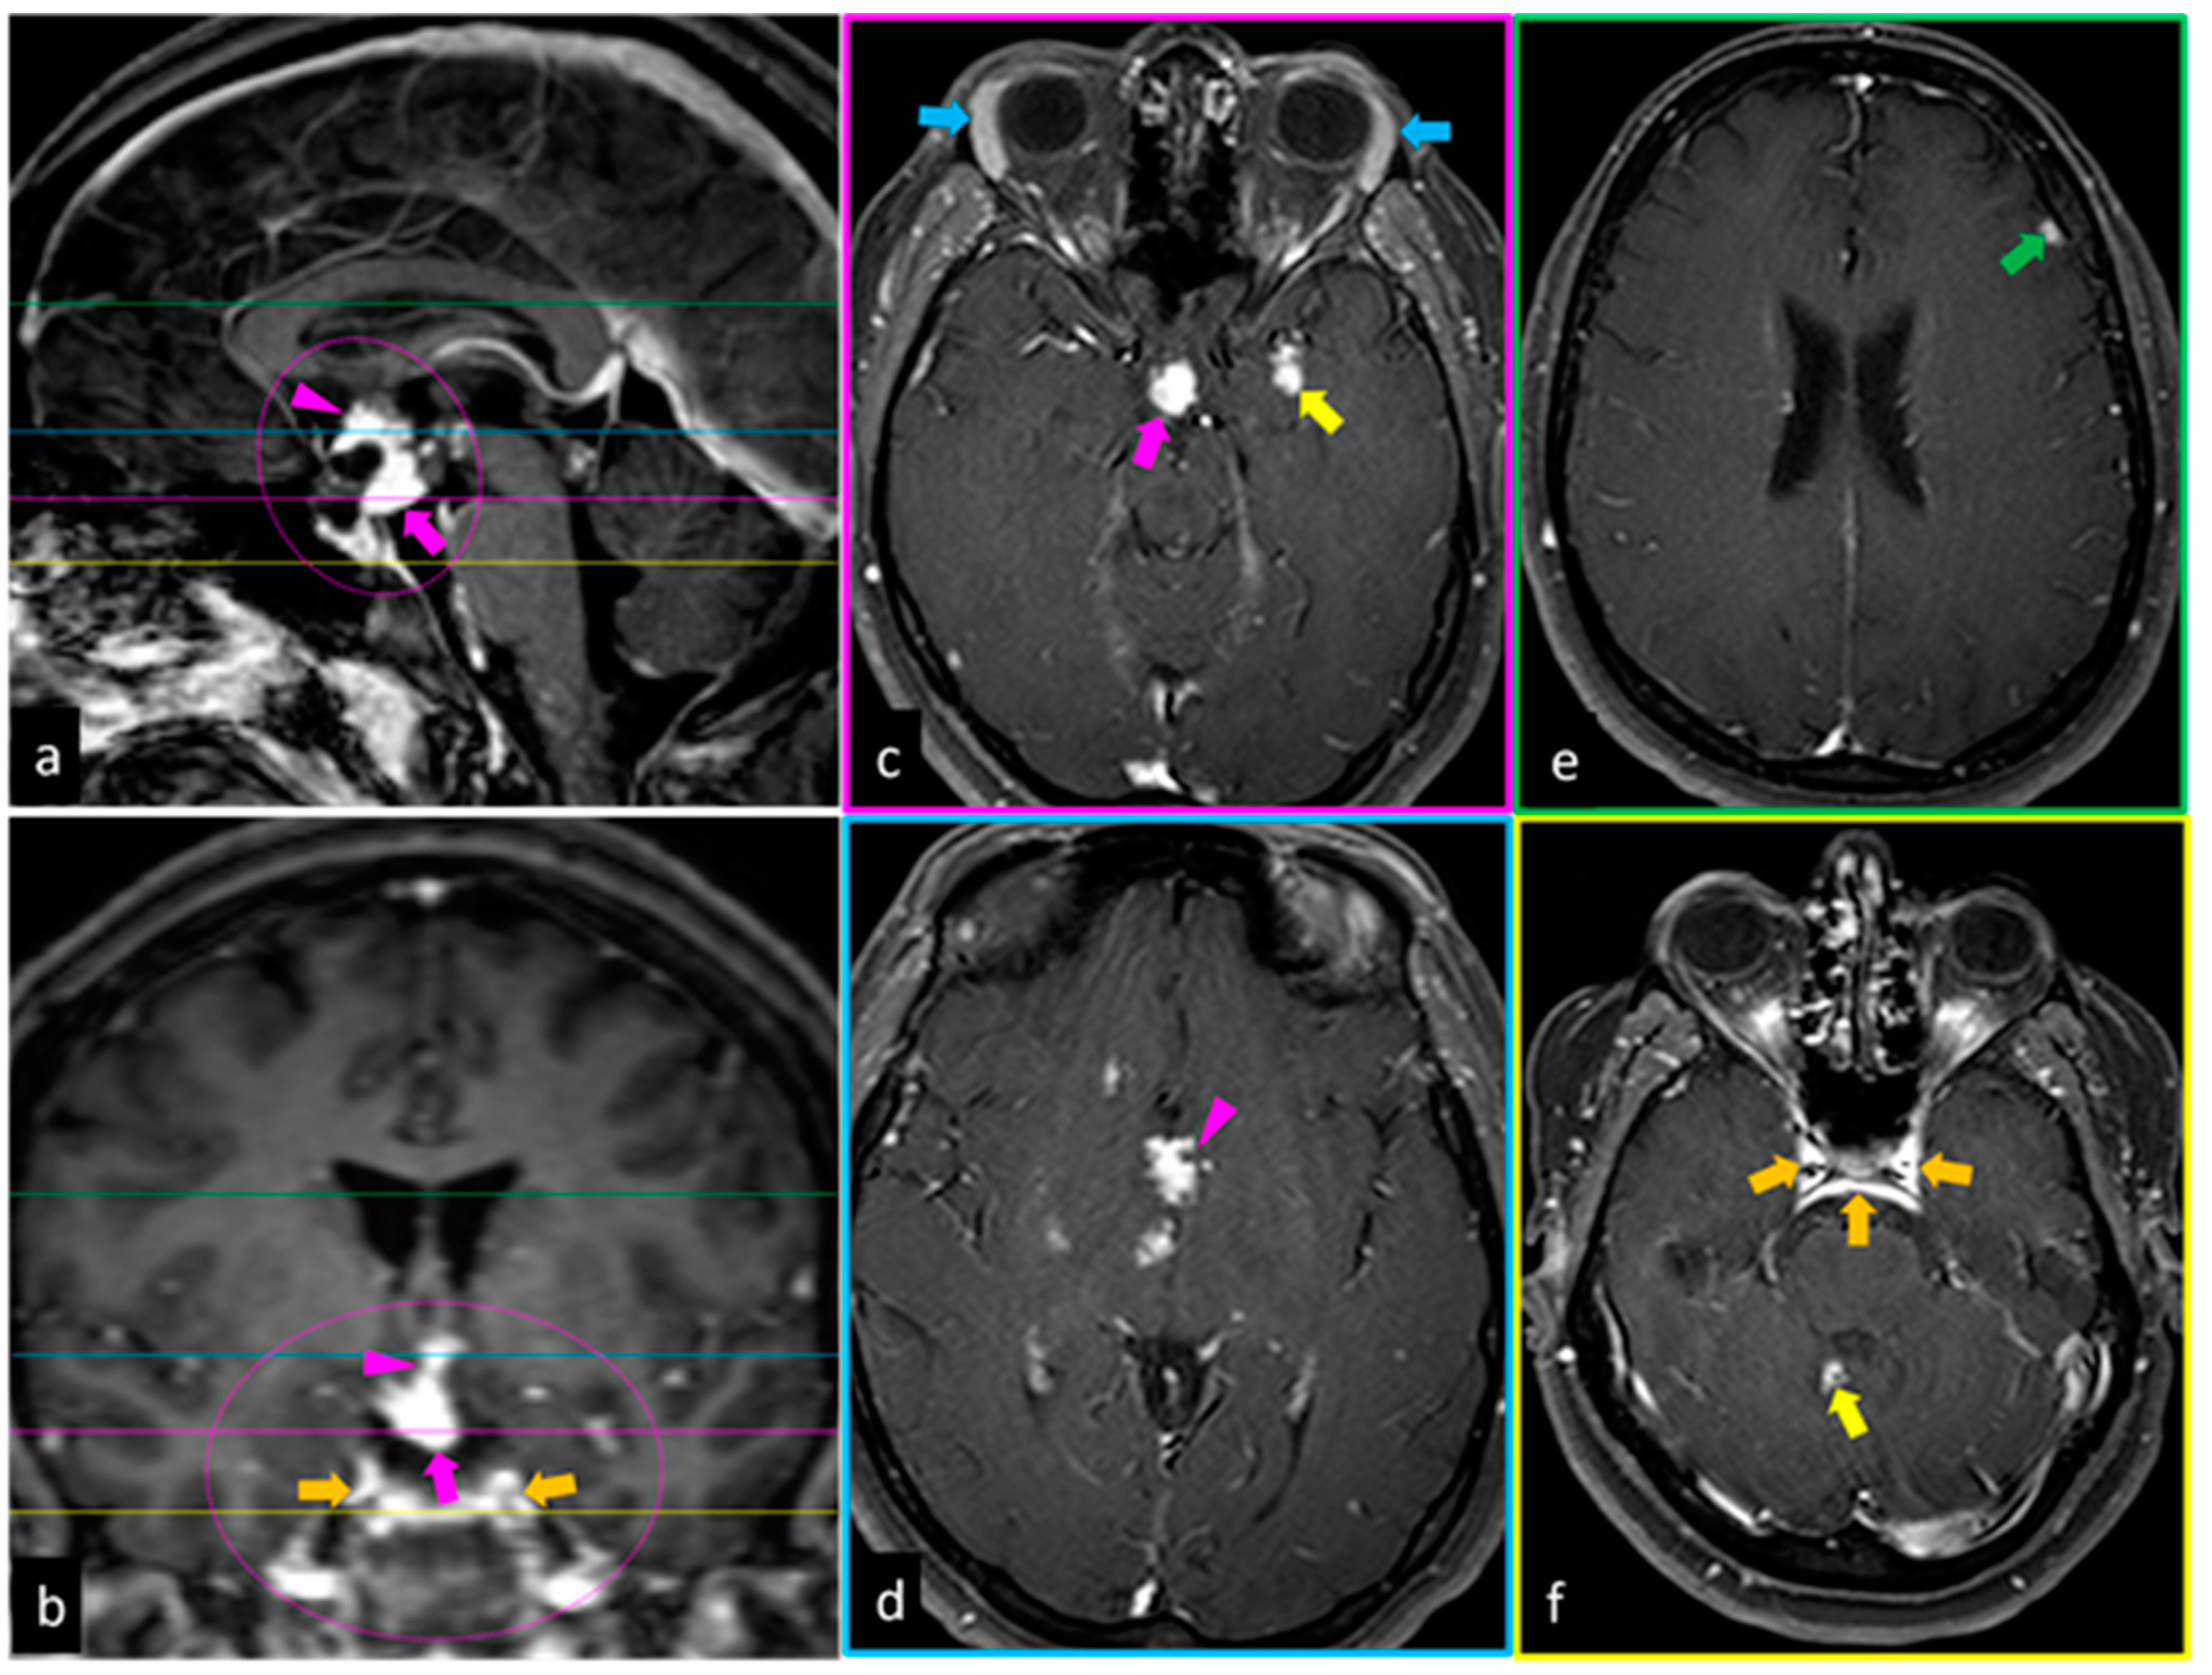

4.1. Magnetic Resonance Imaging

- Hayes, W.S.; Sherman, J.L.; Stern, B.J.; Citrin, C.M.; Pulaski, P.D. MR and CT evaluation of intracranial sarcoidosis. AJR Am. J. Roentgenol. 1987, 149, 1043–1049. [Google Scholar] [CrossRef]

- Nowak, D.A.; Widenka, D.C. Neurosarcoidosis: A review of its intracranial manifestation. J. Neurol. 2001, 248, 363–372. [Google Scholar] [CrossRef] [PubMed]

- Smith, J.K.; Matheus, M.G.; Castillo, M. Imaging manifestations of neurosarcoidosis. AJR Am. J. Roentgenol. 2004, 182, 289–295. [Google Scholar] [CrossRef]

- Shah, R.; Roberson, G.H.; Curé, J.K. Correlation of MR imaging findings and clinical manifestations in neurosarcoidosis. AJNR Am. J. Neuroradiol. 2009, 30, 953–961. [Google Scholar] [CrossRef]